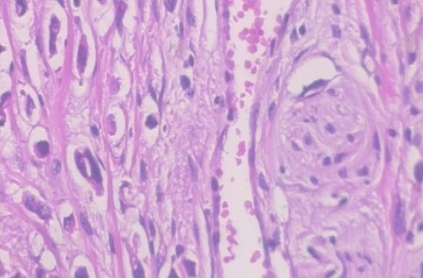

Background: Breast cancer has the highest prevalence in women globally. The classification and diagnosis of breast cancer and its histopathological images have always been a hot spot of clinical concern. In Computer-Aided Diagnosis (CAD), traditional classification models mostly use a single network to extract features, which has significant limitations. On the other hand, many networks are trained and optimized on patient-level datasets, ignoring the application of lower-level data labels. Method: This paper proposes a deep ensemble model based on image-level labels for the binary classification of benign and malignant lesions of breast histopathological images. First, the BreakHis dataset is randomly divided into a training, validation and test set. Then, data augmentation techniques are used to balance the number of benign and malignant samples. Thirdly, considering the performance of transfer learning and the complementarity between each network, VGG-16, Xception, Resnet-50, DenseNet-201 are selected as the base classifiers. Result: In the ensemble network model with accuracy as the weight, the image-level binary classification achieves an accuracy of $98.90\%$. In order to verify the capabilities of our method, the latest Transformer and Multilayer Perception (MLP) models have been experimentally compared on the same dataset. Our model wins with a $5\%-20\%$ advantage, emphasizing the ensemble model's far-reaching significance in classification tasks. Conclusion: This research focuses on improving the model's classification performance with an ensemble algorithm. Transfer learning plays an essential role in small datasets, improving training speed and accuracy. Our model has outperformed many existing approaches in accuracy, providing a method for the field of auxiliary medical diagnosis.